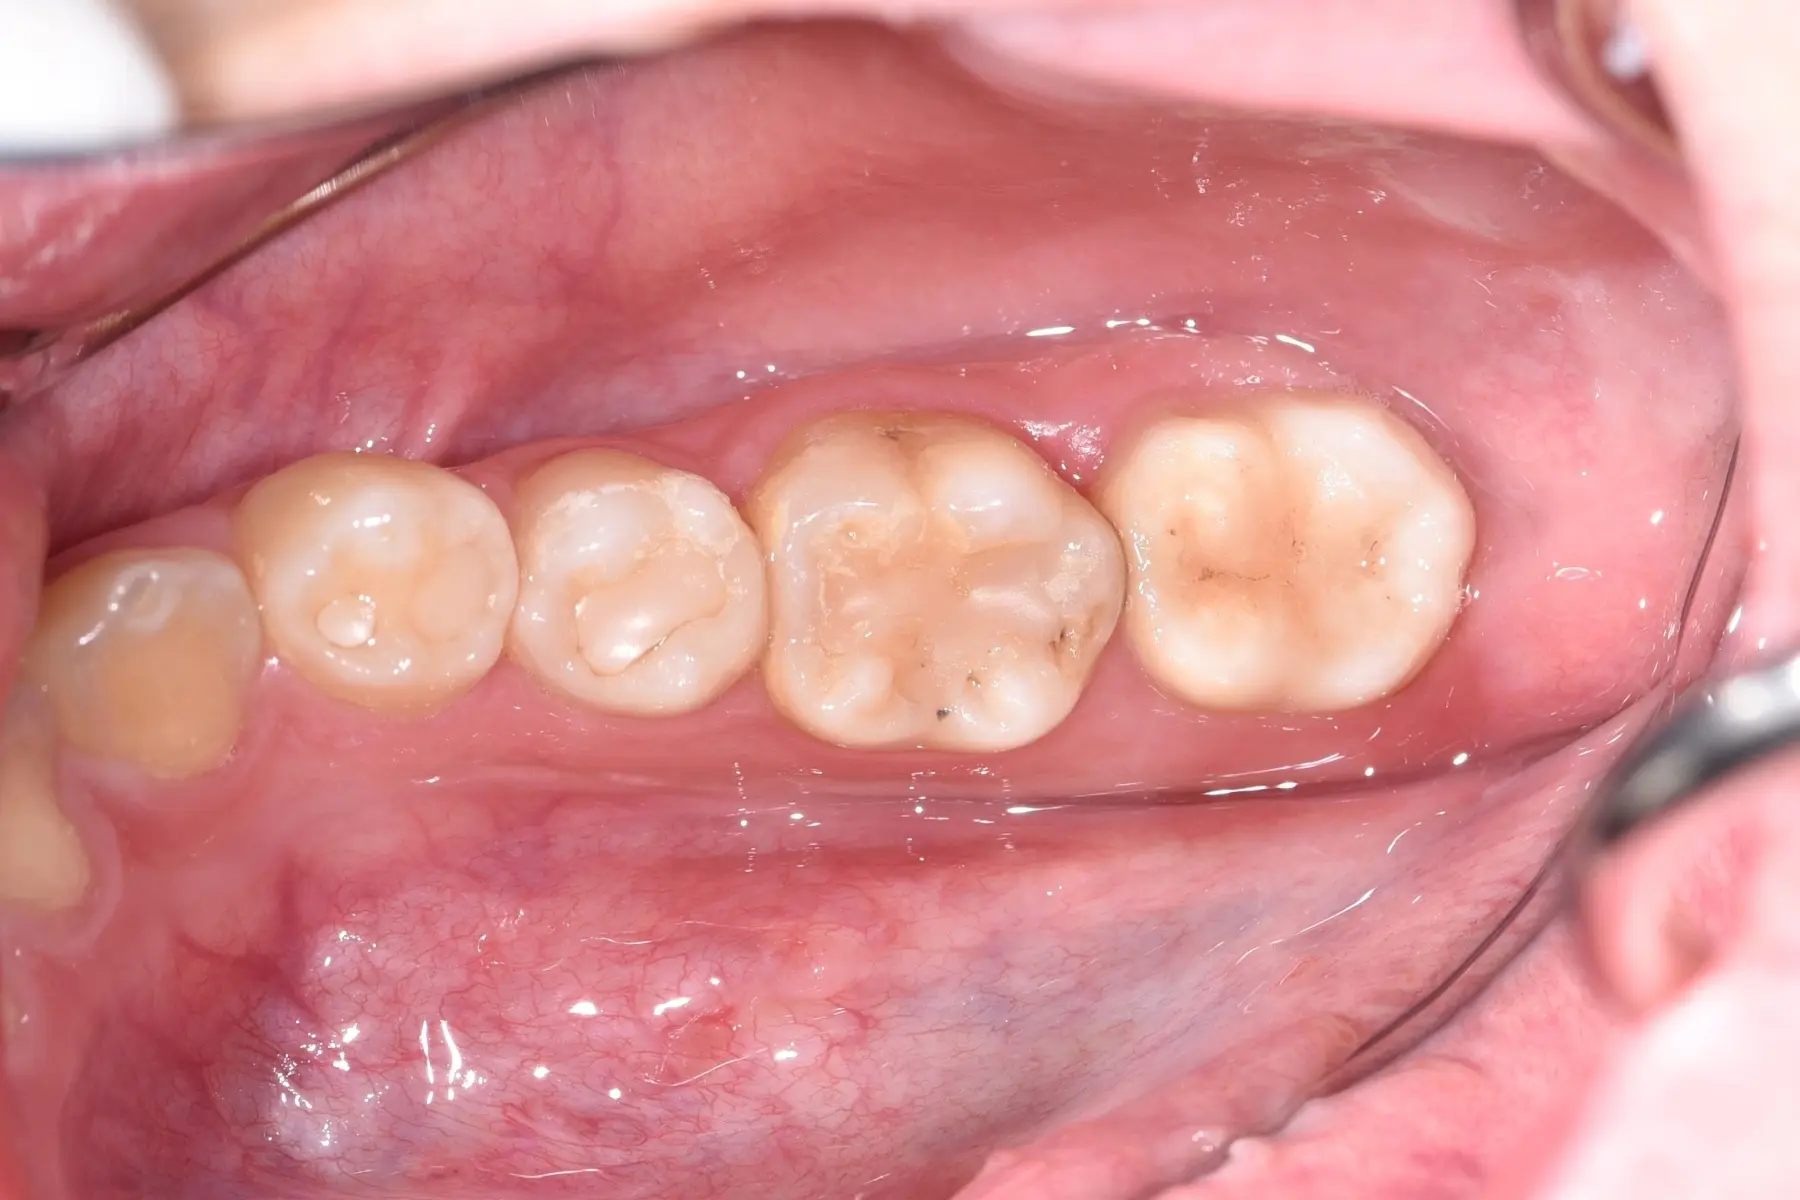

• 自體牙移植術前

自體牙移植術後

口腔外科/自體牙移植

主治醫師

• 林明志

治療時間

單次療程

主訴

矯正治療前發現牙齒嚴重蛀牙,無法保留